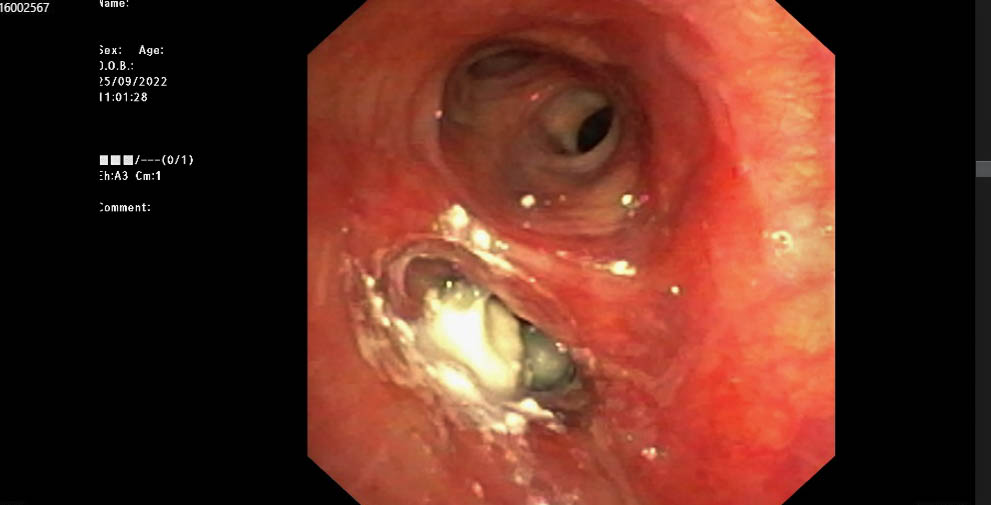

Bệnh nhân được bác sĩ thăm khám và xử trí ban đầu. Kết quả chụp CT ngực có tái tạo 3D phát hiện dị vật đường thở ở thùy dưới phổi bên trái, bệnh nhân nhanh chóng được tiến hành nội soi gắp dị vật có phối hợp chuyên gia Hà Nội. Quá trình thực hiện phát hiện, lòng phế quản có một phần viên thuốc, ekip đã tiến hành sử dụng rọ để lấy đồng thời tiếp tục bơm nước rửa nhiều lần và lấy nốt phần còn lại ra thành công. Sau gắp, bệnh nhân đã hết tức ngực, hết khó thở và ổn định.

- Hình ảnh dị vật qua nội soi của bệnh nhân